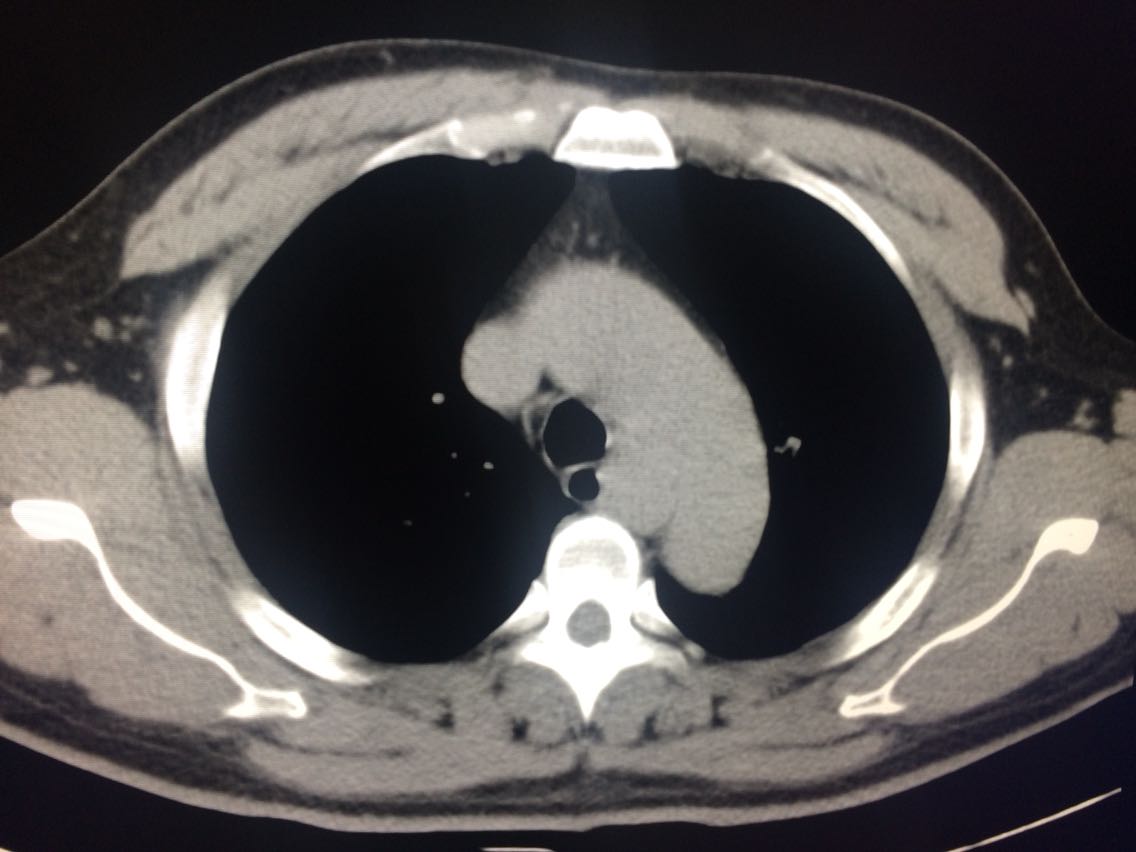

一例食管平滑肌瘤的影像表现

食管平滑肌瘤

男,48岁 间断返酸2年。 2年前,患者无诱因出现间断返酸,烧心不适,无吞咽困难,恶心,呕吐,呕血,黑便等。口服奥美拉唑治疗,效果不佳。遂入院。 既往高血压病史7年。

入院后做上消化道造影及CT如图。 门诊胃镜提示距门齿26cm处见食管左壁分叶状粘膜下肿物,表面光滑。

考虑食管平滑肌瘤。 手术治疗。